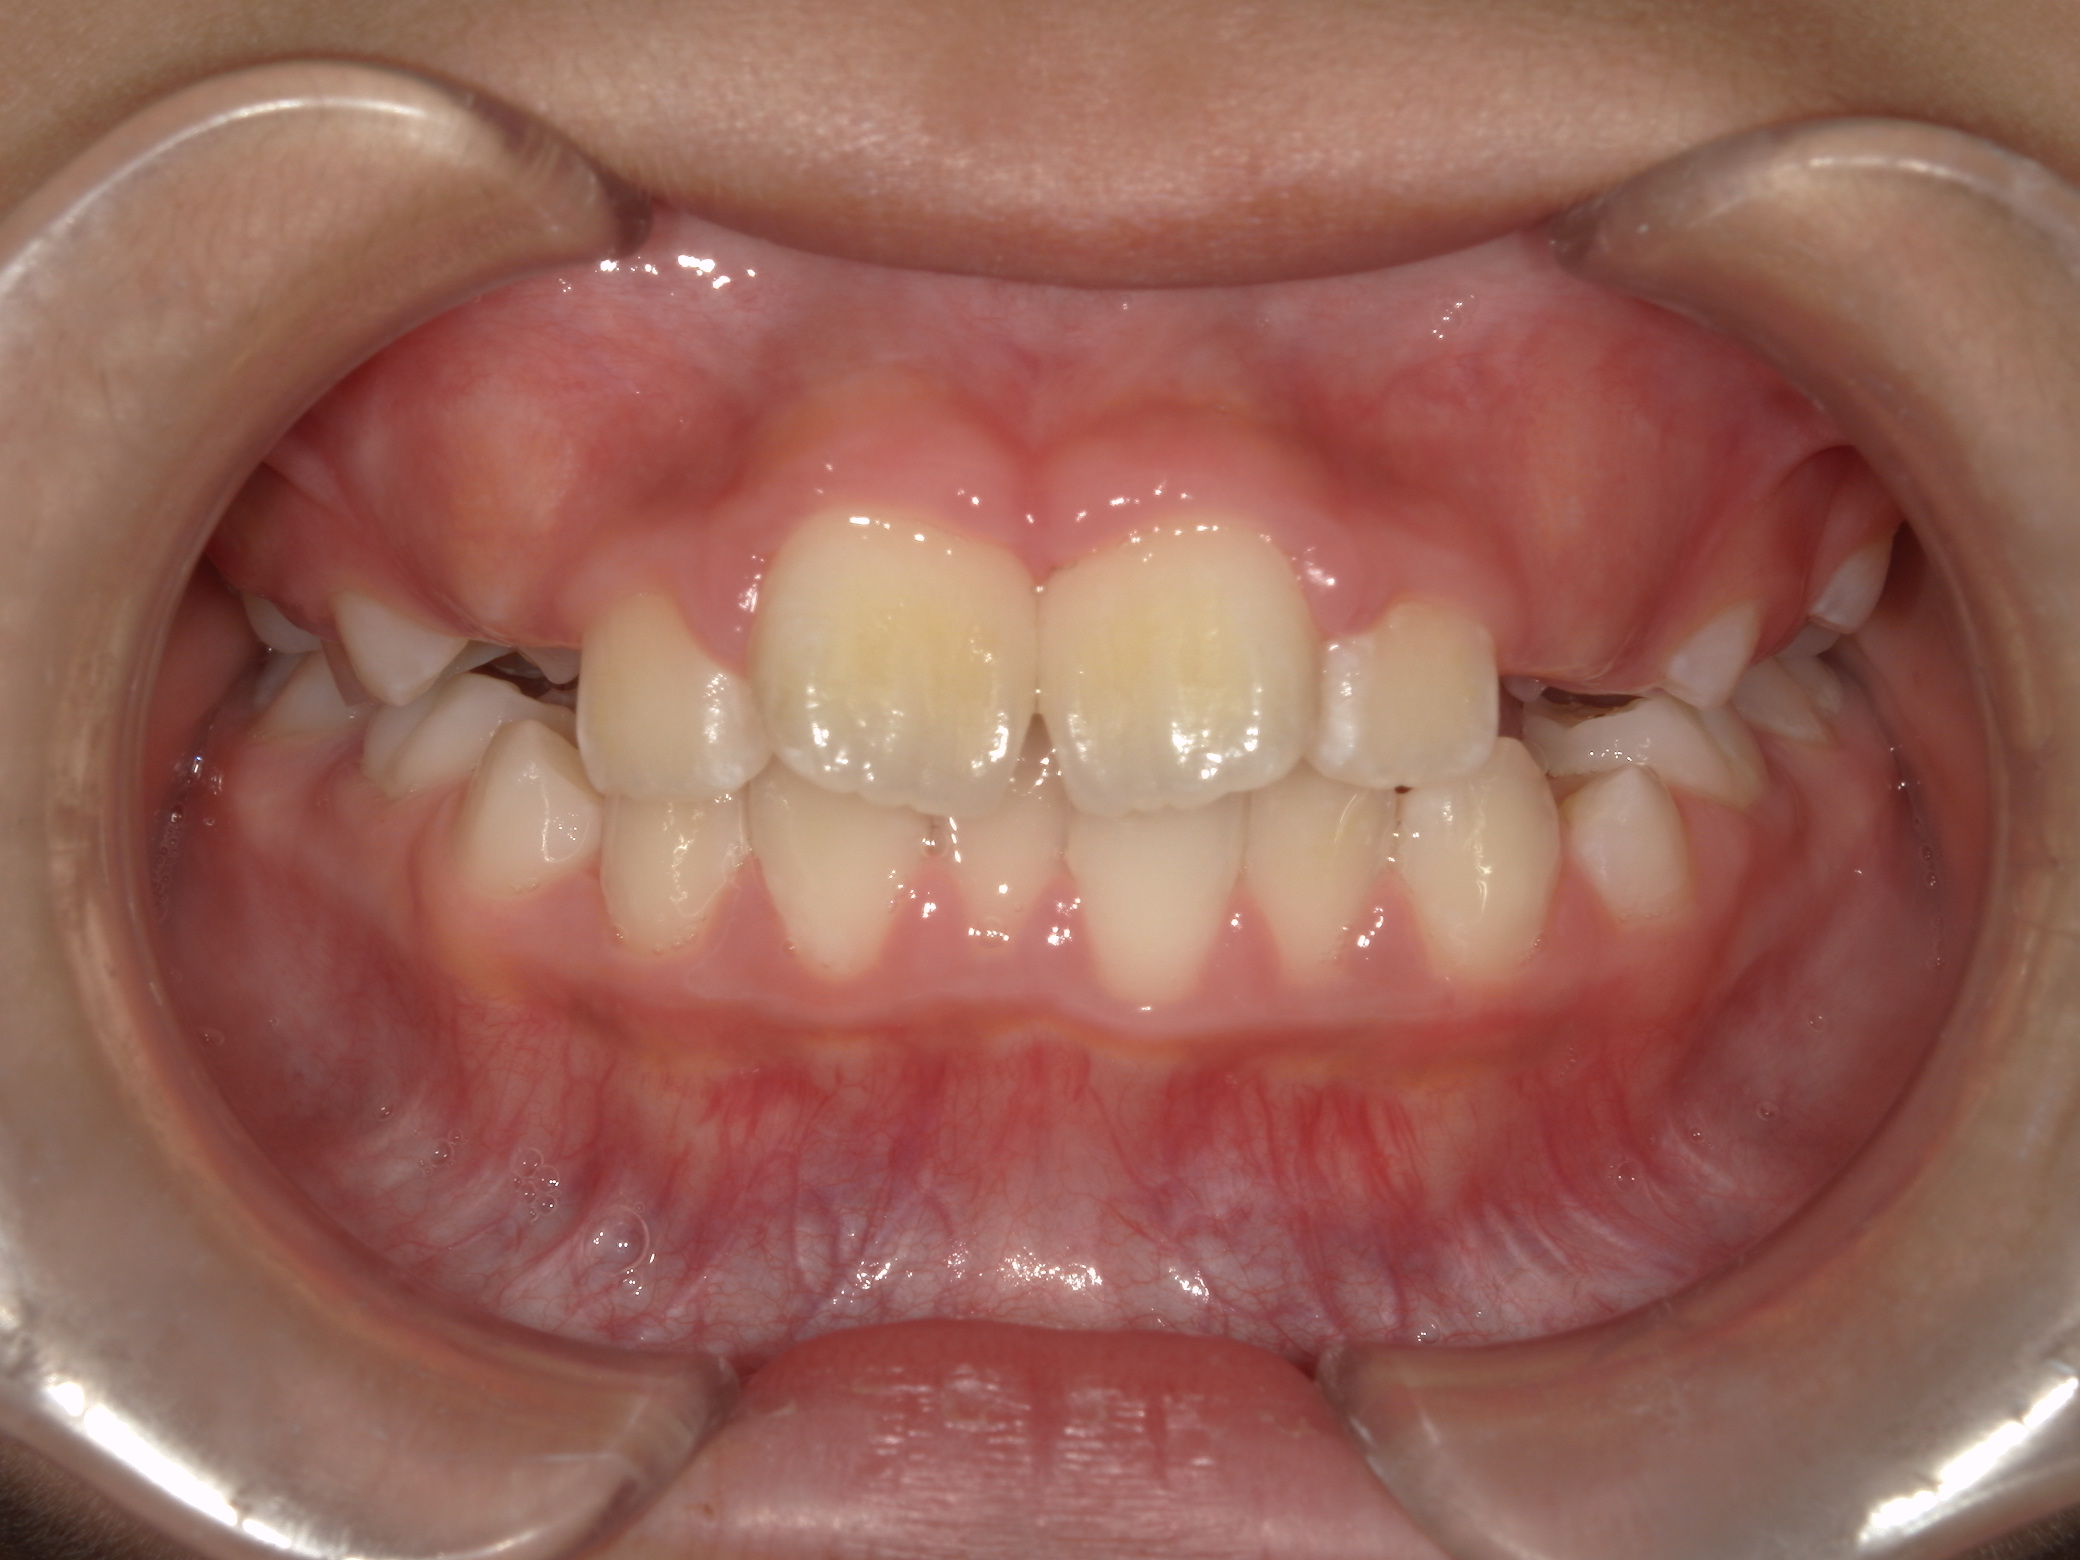

早期矯正治療 反対咬合症例②

主訴 | 前歯の噛み合わせが逆で、見た目や食事に違和感があることを心配されて来院されました。 |

---|---|

診断結果 | 7歳8か月の男児 前歯の反対咬合診断 |

治療内容 |

|

治療後の経過 | 早期矯正治療は11歳5か月で終了し、現在は3〜4か月ごとの定期検診で経過観察中で、今後本格的な矯正治療へ移行予定です。 |

治療期間 | 3年6か月 |

治療費用 | 430,000円(税別) |